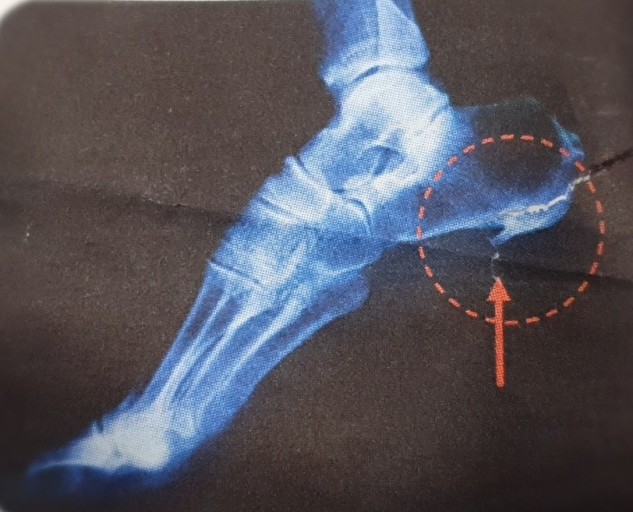

플랜타르 패시아염 (족저근막염)

- 발바닥의 아치에 위치한 두꺼운 섬유 조직인 족저근막이 염증이 생기는 질환입니다. 주로 장시간 서 있거나 걷는 경우, 혹은 비만으로 인해 과도한 압력이 가해져 발생합니다. 통증은 주로 아침에 일어났을 때 첫 발을 내딛을 때 가장 심하게 느껴지며, 점차 운동 후에도 나타날 수 있습니다.